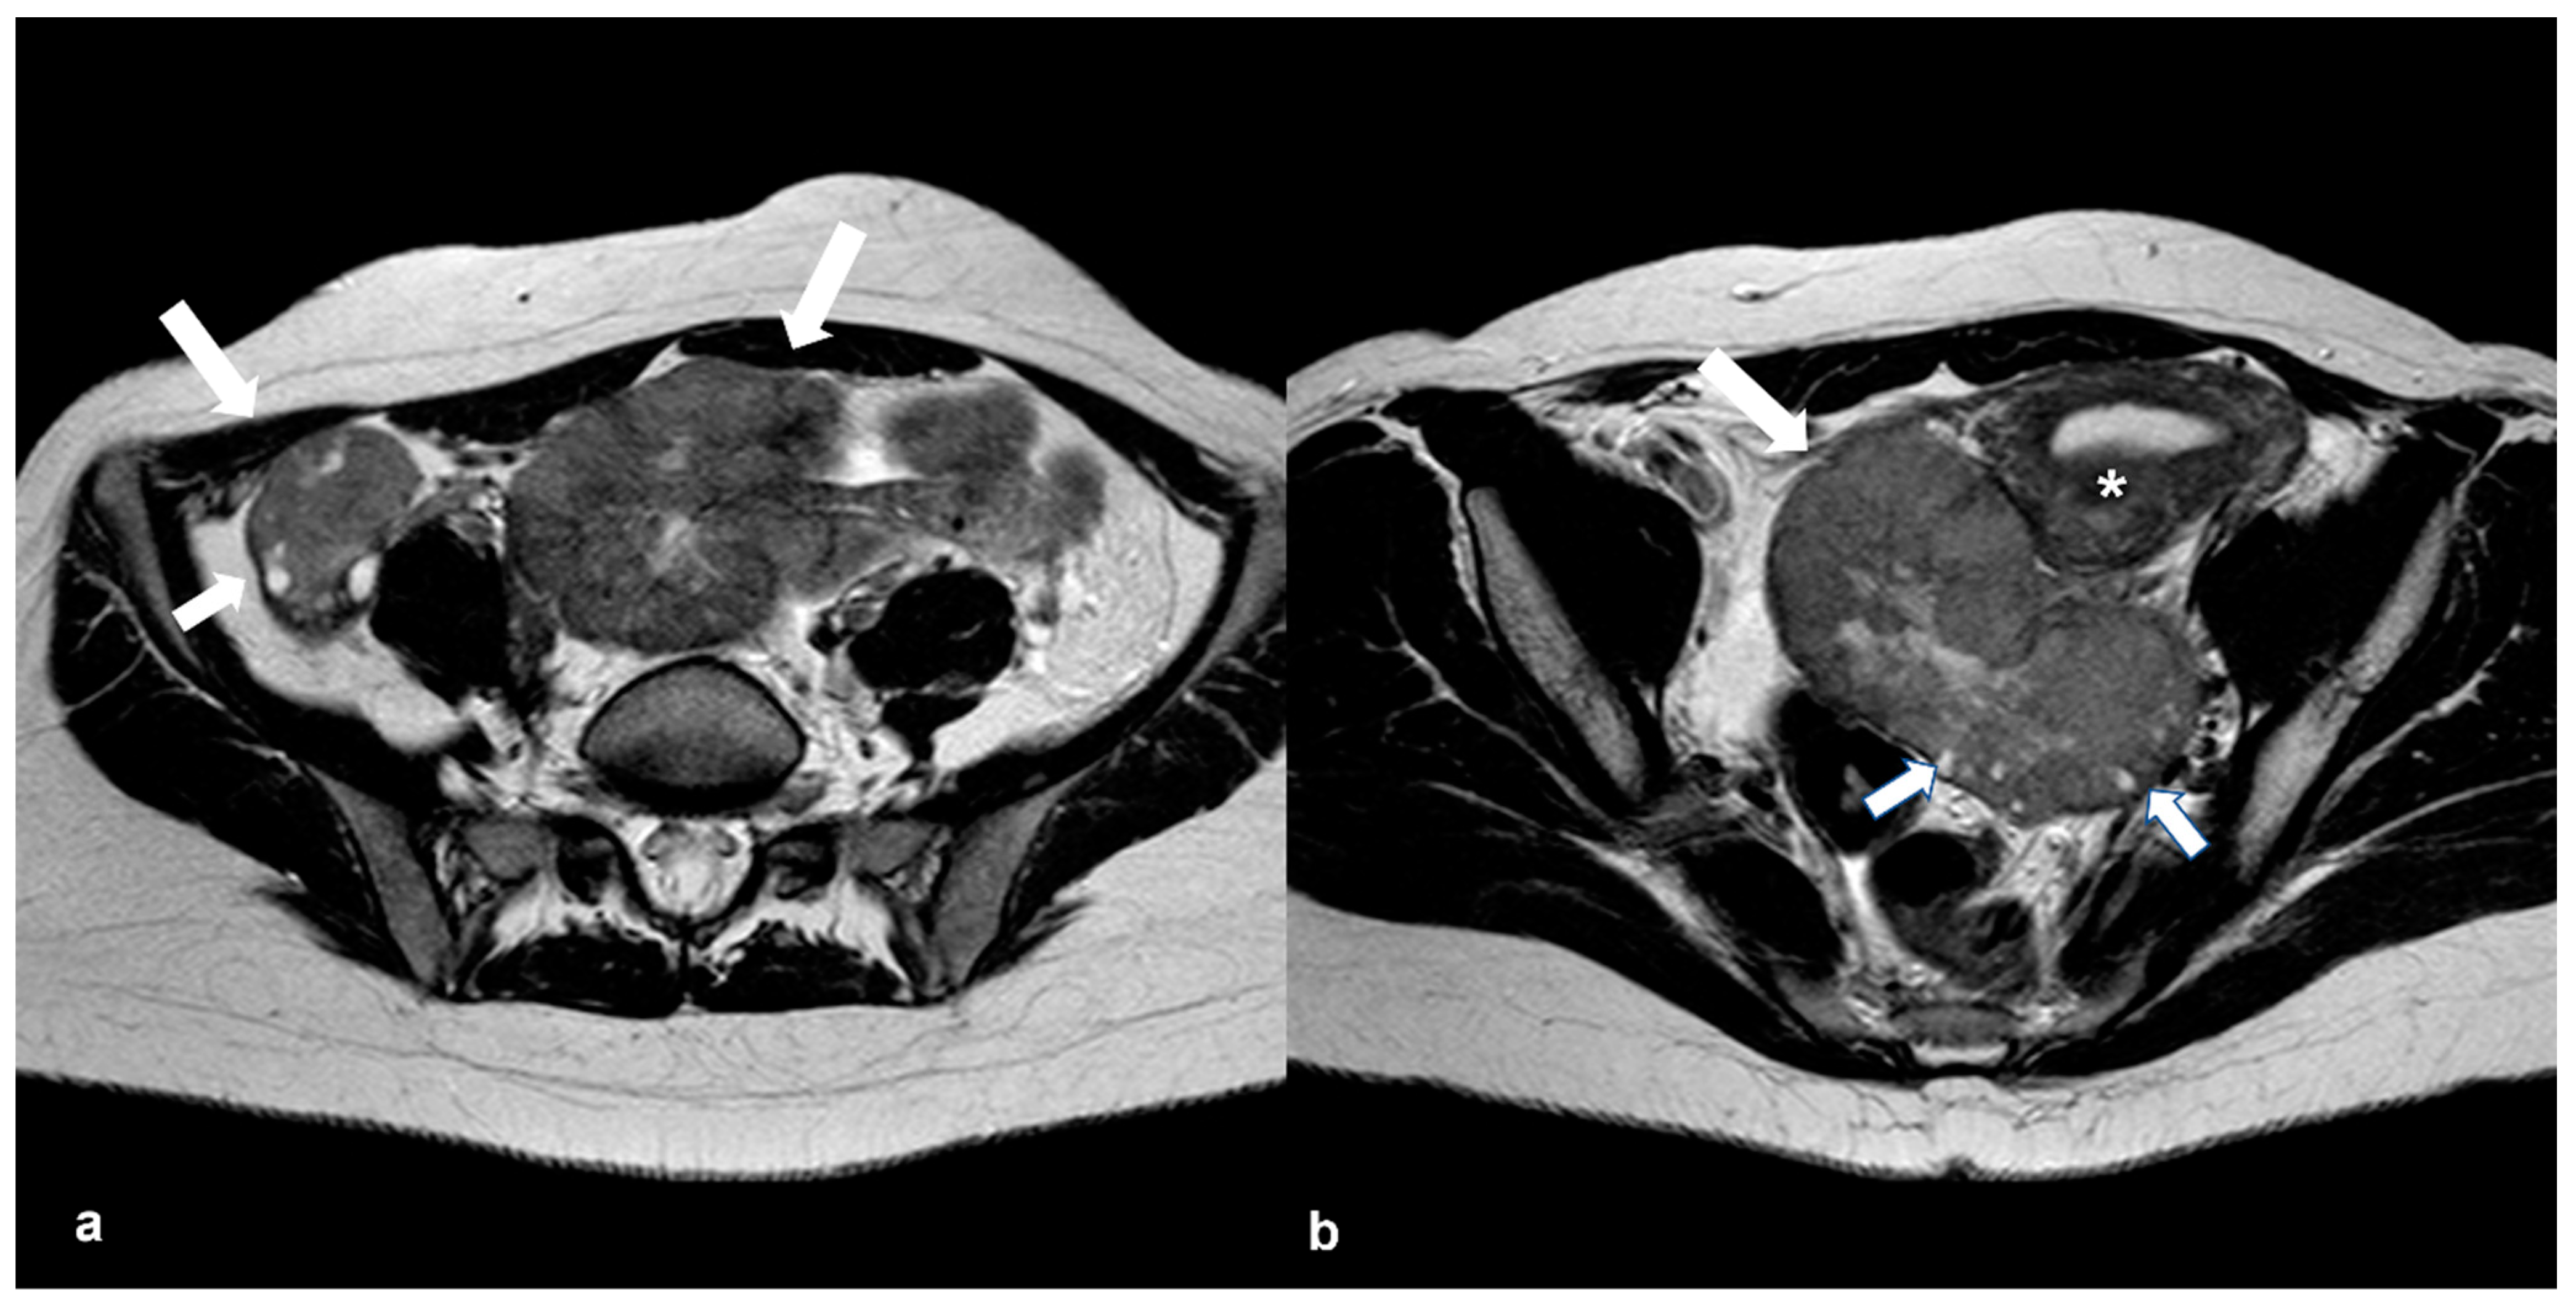

2.1.1. High-Grade Serous Cystadenocarcinoma (HGSC)

2.1.4. Endometrioid Carcinoma and Clear Cell Carcinoma